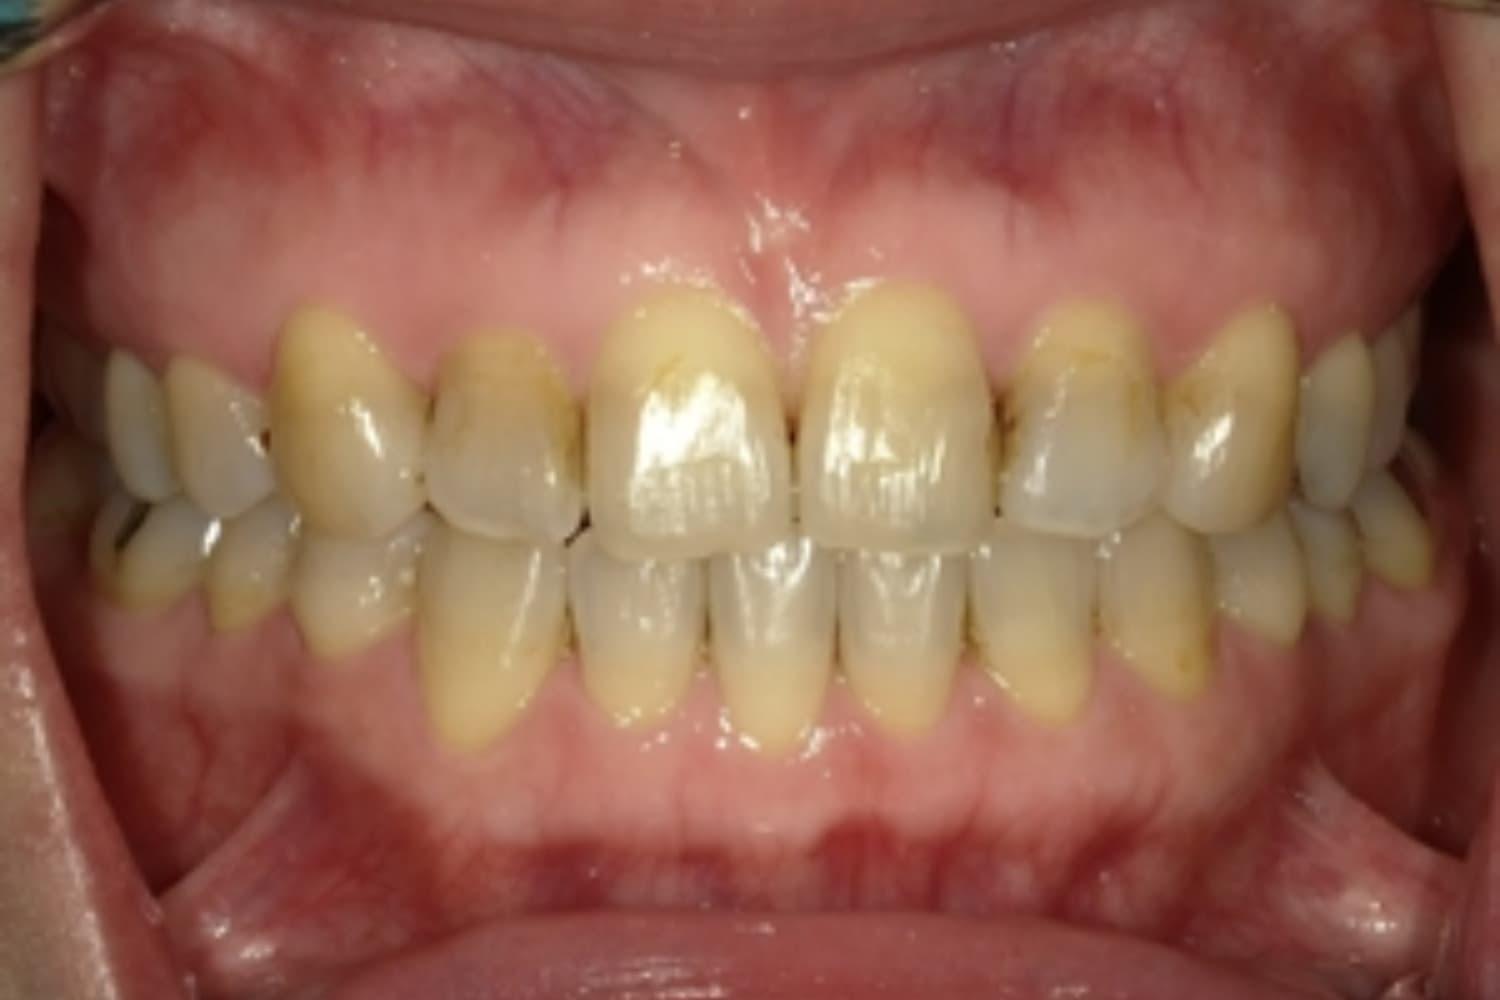

すきっぱ(空隙歯列)

Before

After

気になる前歯の隙間と前歯のガタガタをマウスピース矯正(インビザライン)にて治療

治療期間

1年5カ月

費用

66万円(税込)